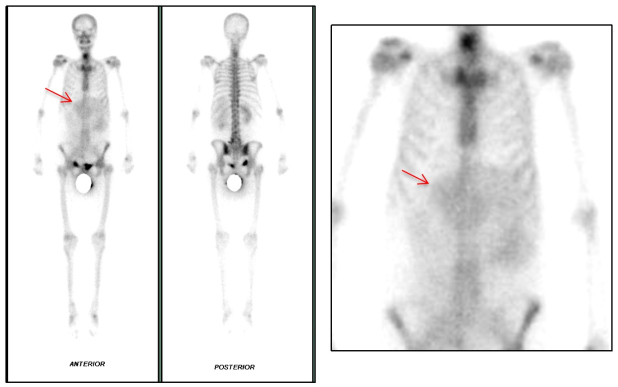

Ante sospecha imagenológica de malignidad se realizó gammagrafía ósea con 99mTc-MDP, sin evidencia de metástasis, pero con la presencia de captación extraósea a nivel abdominal (fig. 1). Se procede a resección quirúrgica de la masa abdominal, encontrando tumor retroperitoneal de aspecto sarcomatoso que compromete estructuras vasculares de la línea media y siembras peritoneales, logrando resecar aproximadamente el 60% de la lesión tumoral.

Se presenta el caso de una paciente en la sexta década de la vida con presencia de una gran masa retroperitoneal, la cual se evidencia como una captación extra esquelética en la gammagrafía ósea con 99mTc-MDP, tratándose de un liposarcoma desdiferenciado asociado a necrosis importante.